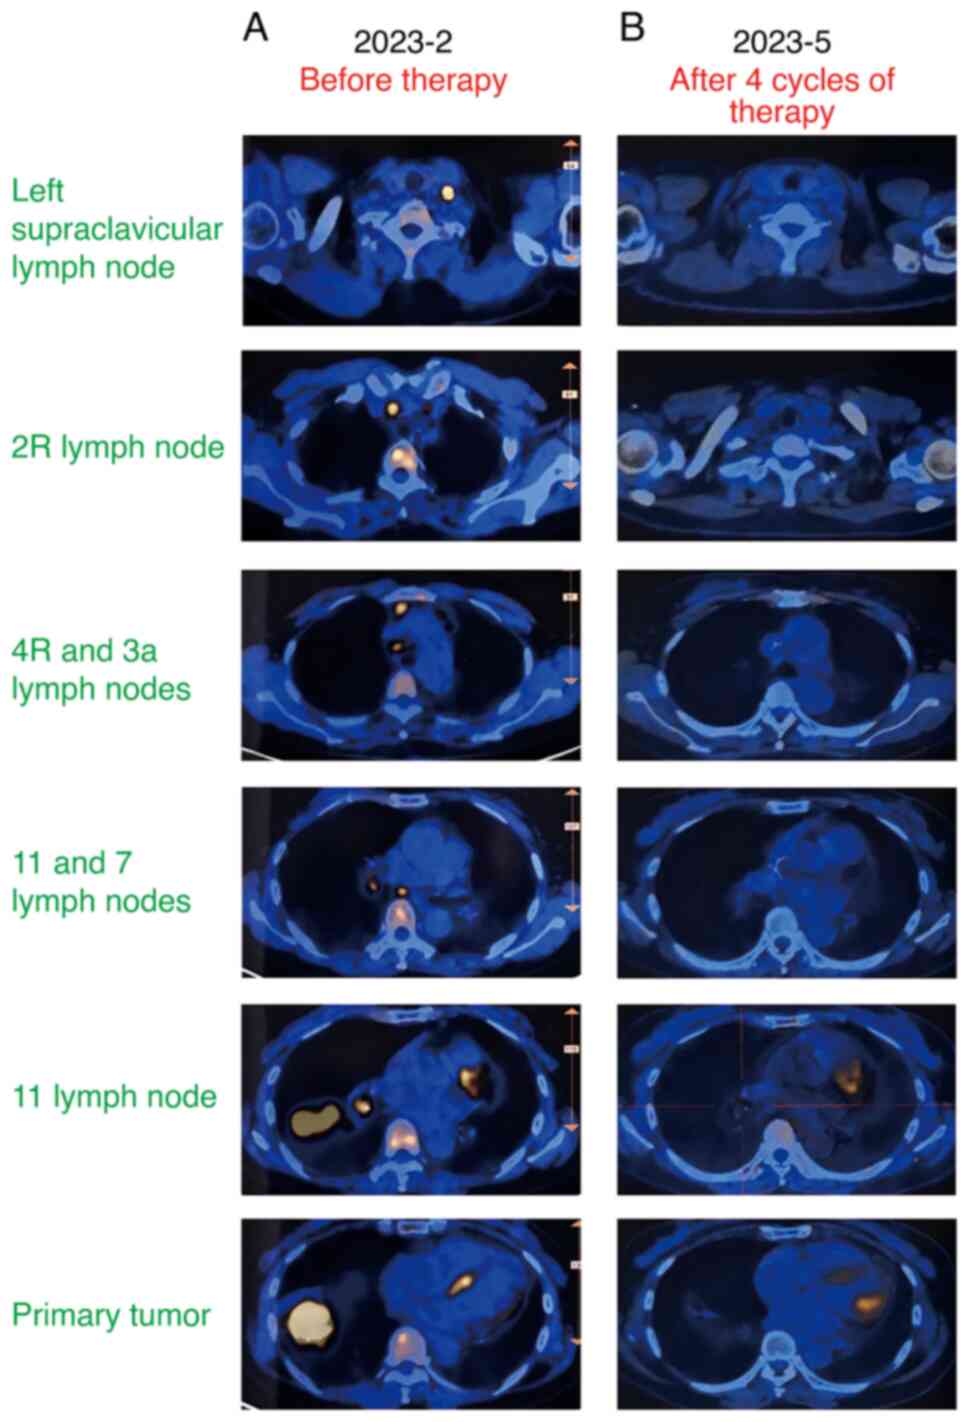

Successful conversion surgery following tislelizumab with chemotherapy in a patient with stage IIIC lung adenocarcinoma harboring RET fusions: A case report and review of the literature

Immune checkpoint inhibitors (ICIs) have emerged as a beacon of hope for most patients with stage III non‑small cell lung cancer (NSCLC) who are no longer surgical candidates. However, the literature on the use of immunotherapy in patients with NSCLC with rearranged during transfection (RET) gene fusions is scant. The present study reports the case of a 61‑year‑old female patient, diagnosed with stage IIIC lung adenocarcinoma, exhibiting two RET gene fusions and high programmed death‑ligand 1 expression. Following four treatment cycles of tislelizumab in combination with pemetrexed and cisplatin, the patient was successfully downstaged, enabling radical surgery. The post‑operative pathology analysis indicated a major pathologic response. This case study contributes to the growing body of evidence supporting the use of ICIs in treating locally advanced NSCLC with RET gene fusions.